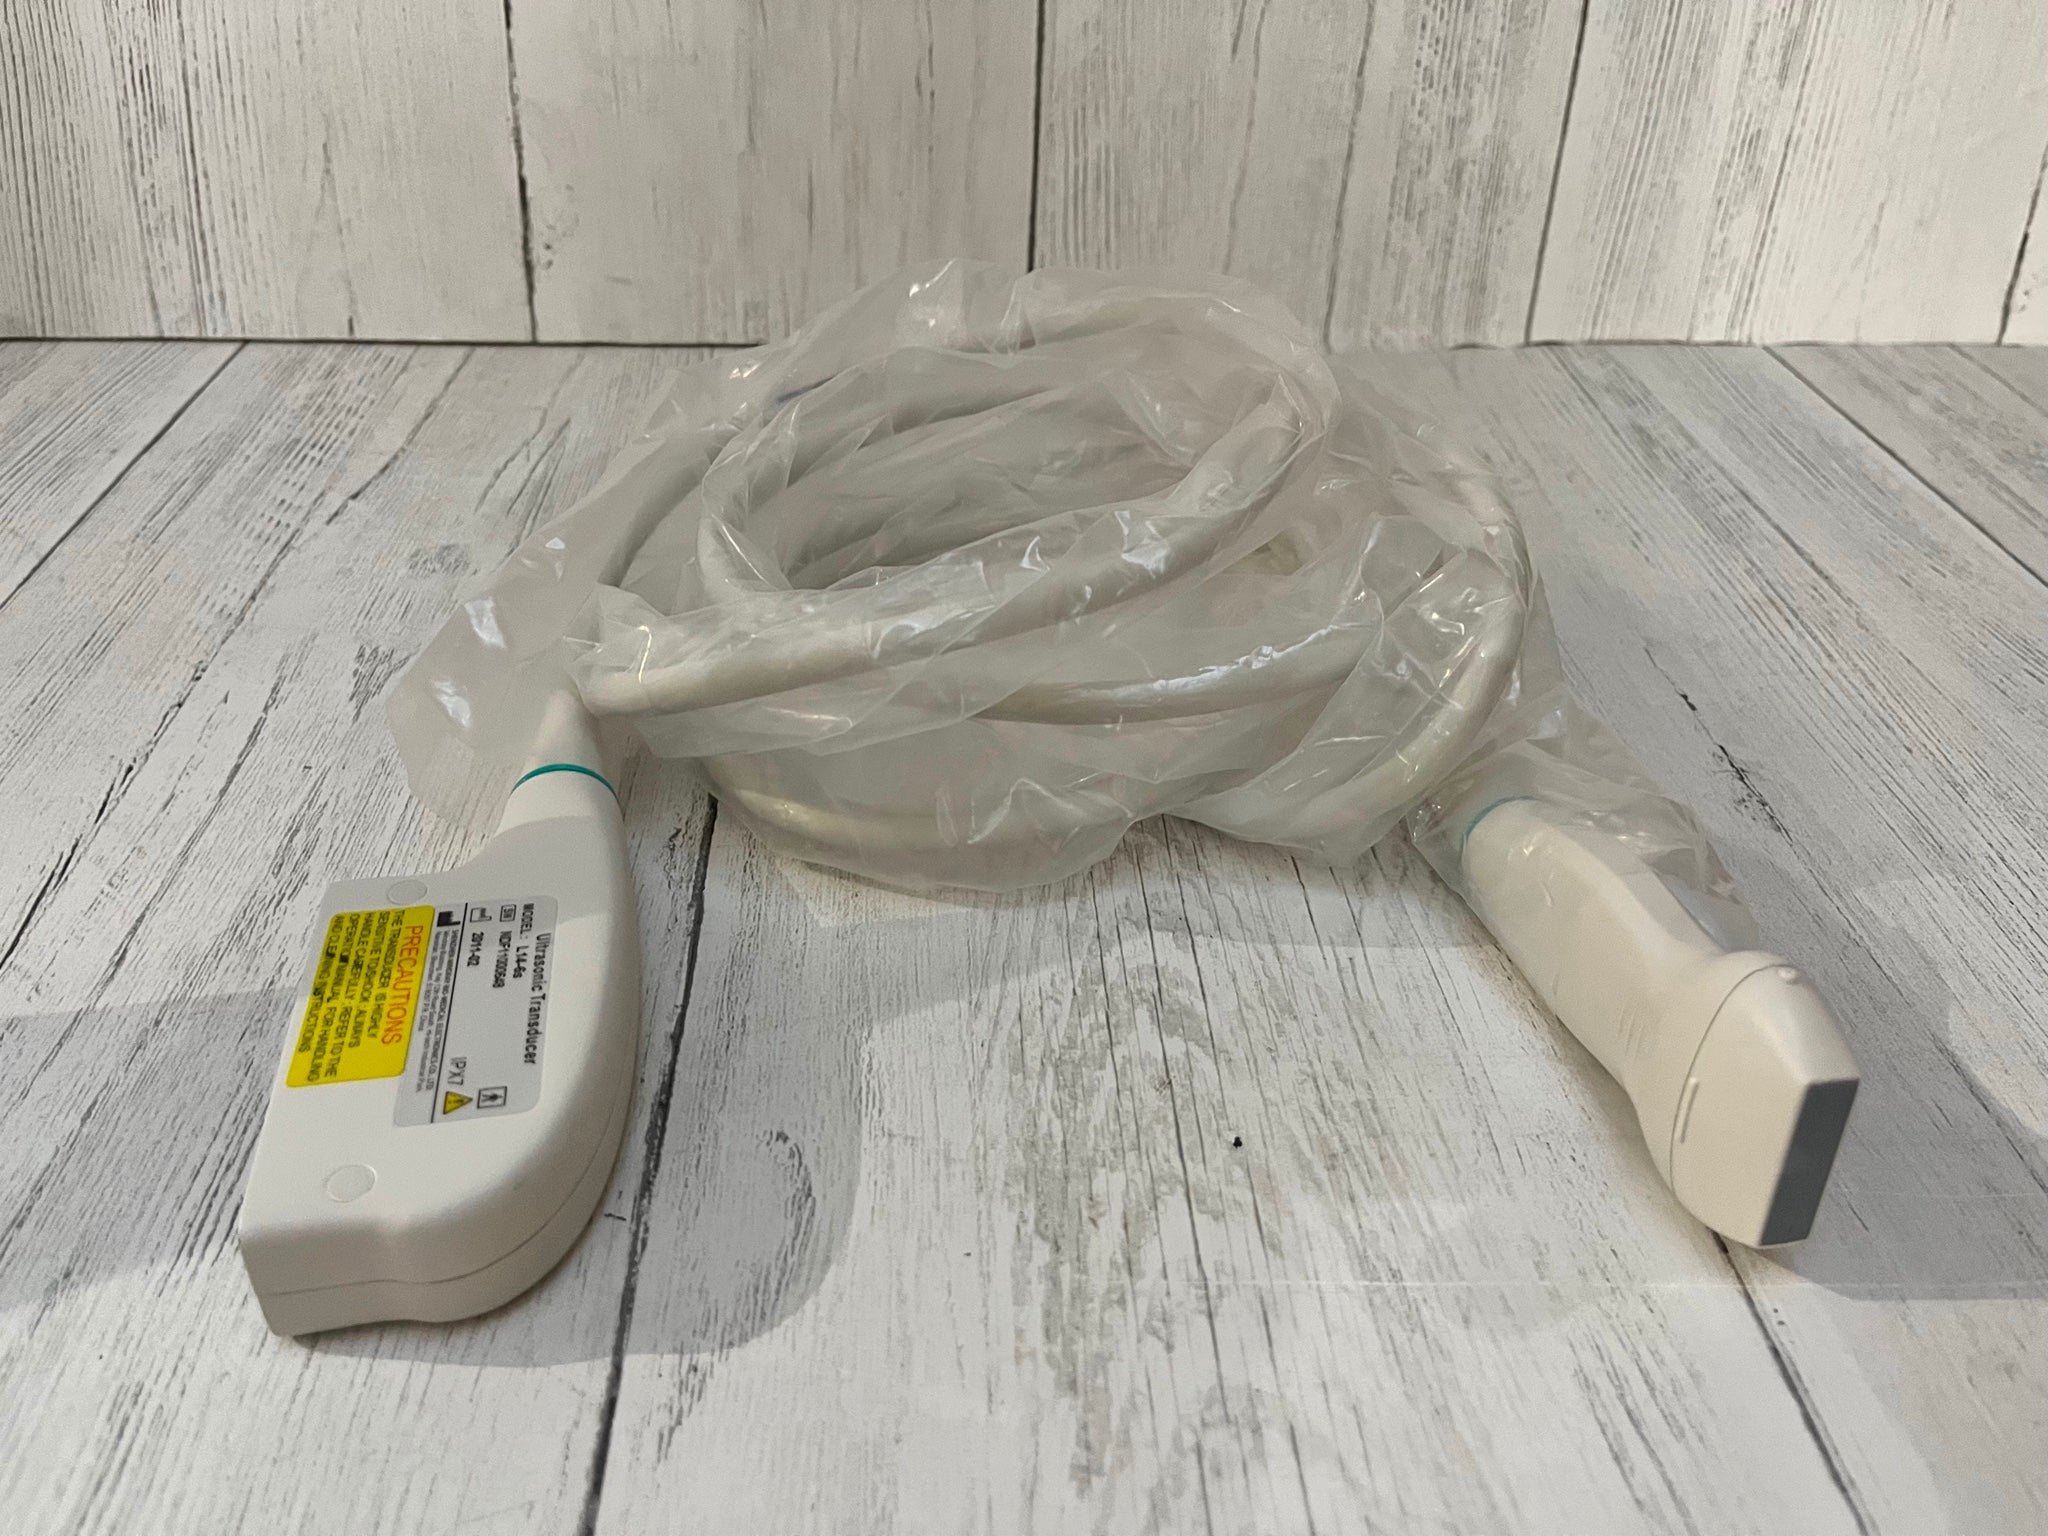

Probe Function: 3.5MHZ convex, abdominal organs

The Diagnostic Ultrasound Scanner provides a comprehensive solution for medical practitioners. It includes both convex and transvaginal probes, allowing for versatile imaging options. With the ability to create detailed images of various organs, this machine significantly improves diagnostic accuracy. Moreover, doctors can perform thorough examinations quickly and easily, so they can identify medical conditions early. As a result, patients receive timely care that can lead to better health outcomes.